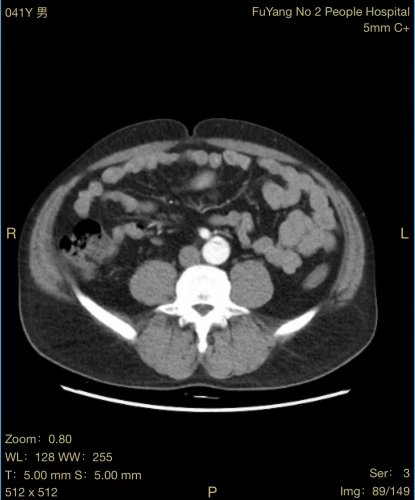

患者张某,男性,41岁,颍州区九龙镇居民,2020年因主动脉夹层在市第二人民医院血管外科行胸主动脉覆膜支架腔内隔绝术,术后恢复尚可,1月前在进行重体力劳动后,出现腰背部疼痛不适,复查主动脉CTA,考虑腹主动脉夹层动脉瘤。

由于患者手术情况复杂,血管外科团队与介入导管室、麻醉科等积极沟通并进行充分的手术准备,在多学科相互配合下,为患者行腹主动脉覆膜支架置入及“四开窗”术,手术顺利,完美隔绝夹层破口,保留腹腔干、肠系膜上动脉、双肾动脉,患者恢复良好。